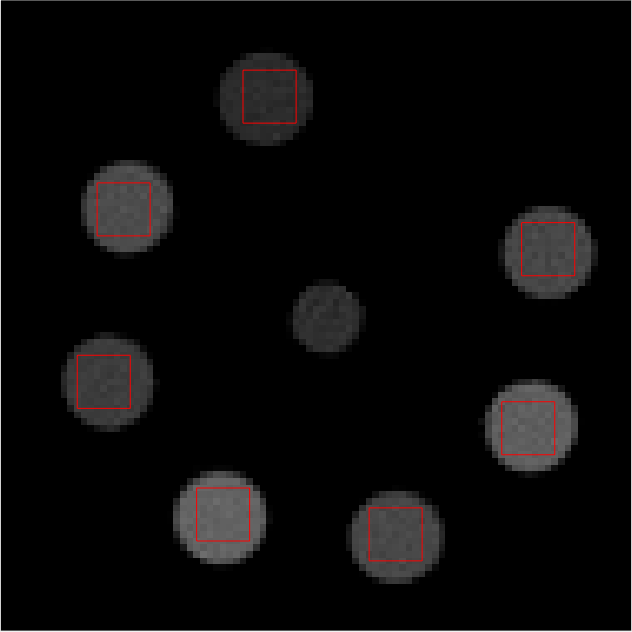

Individual reconstructions from every bin were first performed with scalar MBIR. This furnished 555 LAC images, each from a different energy bin. 101010 slices of each LAC image volume were used to compute \mathcal{M}. The mixing matrix was computed from ROIs shown in red in Fig 2. The following equation must be satisfied ideally

Refer to caption

(a)

(b)

(c)

(d)

(e)

Figure 2: Middle slice of LAC image reconstruction of each energy bin sinogram for mixing matrix estimation. Display window [0, 0.1]

LABEL:sub@fig:En1 Bin1:7.019.0keV7.019.0𝑘𝑒𝑉7.0-19.0\ keV, LABEL:sub@fig:En2 Bin2: 19.029.0keV19.029.0𝑘𝑒𝑉19.0-29.0\ keV, LABEL:sub@fig:En3 Bin3: 29.038.8keV29.038.8𝑘𝑒𝑉29.0-38.8\ keV, LABEL:sub@fig:En4 Bin4: 38.851.1keV38.851.1𝑘𝑒𝑉38.8-51.1\ keV, LABEL:sub@fig:En5 Bin5: 51.182.6keV51.182.6𝑘𝑒𝑉51.1-82.6\ keV